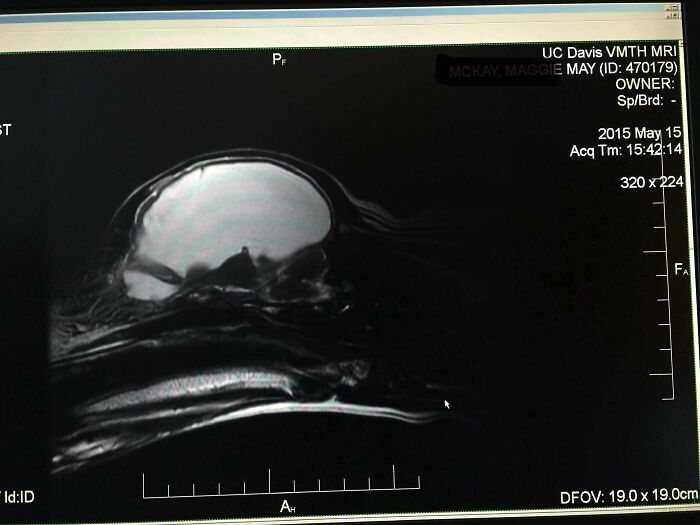

After 6 Years, We Found Out Our Dog’s Brain Was Mostly... Empty

We had this dog for six years and she seemed pretty normal - even had puppies and all. But after a seizure, vet tests showed she had almost no brain! Turns out 95% of the space in her head was just fluid (the white part in the MRI). She was a real medical mystery who held it together until 12 years old, even with nearly no brain!